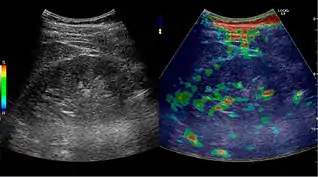

Solid malignant tumors in the kidney do not exhibit specific enhancement patterns like some liver lesions, and no valid enhancement criteria between benign and malignant renal lesions have been proposed. However, CEUS is used in some patients after ablation of renal cell carcinoma to evaluate contrast uptake in the treated area (Figure 30).

Elastography is a US method to visualize the elasticity of tissue. Preliminary reports on US elastography used on transplanted kidneys to evaluate cortical fibrosis have been published showing promising results (Figure 32).[1]

Figure 32. Strain elastography of a normal kidney. Red depicts soft areas, and blue depicts hard areas relative to the entire elastography image. Note that the medulla is softer than the cortex. A color bar is shown to the left of the image, where "S" and "H" denote soft and hard tissue, respectively.[1]